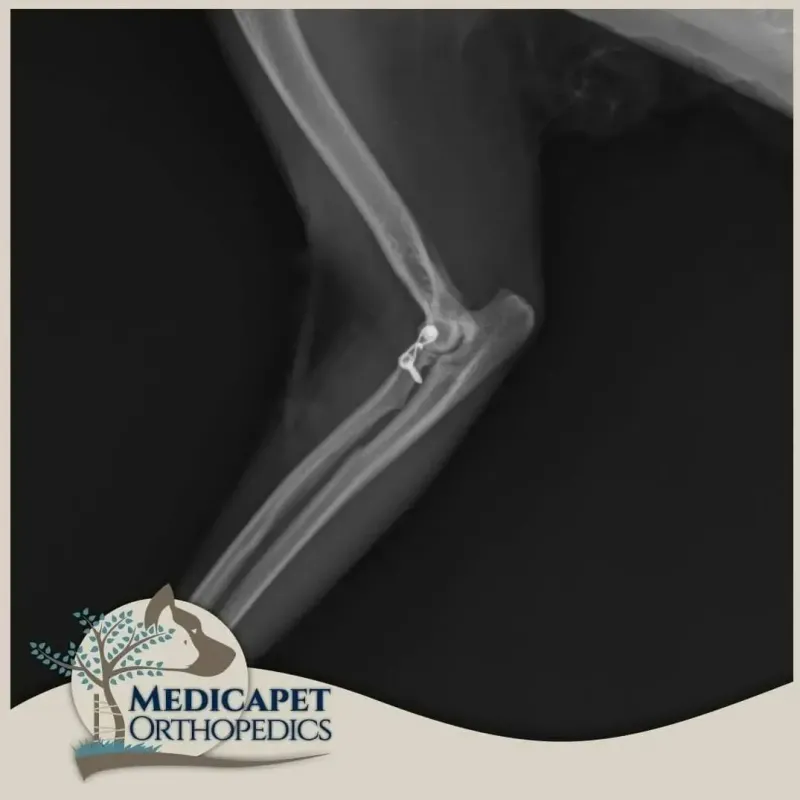

Dirseği saran bağlar ve eklem kapsülünün ağır hasarlı olmadığı durumlarda ameliyatsız kapalı redüksiyon yoluna gidebiliyoruz. Bu tip bir tedavi kısa vadeli etkin takip gerektirir. Dirseğin tekrar çıkması halinde muhtemelen cerrahi tedaviye karar verilecektir. Bağ hasarının yüksek olduğu durumlarda dirsek çıkığının tedavisi açık ameliyat ile yapılır ve hasar gören bağları taklit eden tel, vida ve sentetik bağlardan faydalanırız. Cerrahınız dirsek çıkığının şekline

göre, tedavi seçeneklerini hastanın maksimum faydasına göre değerlendirecektir.